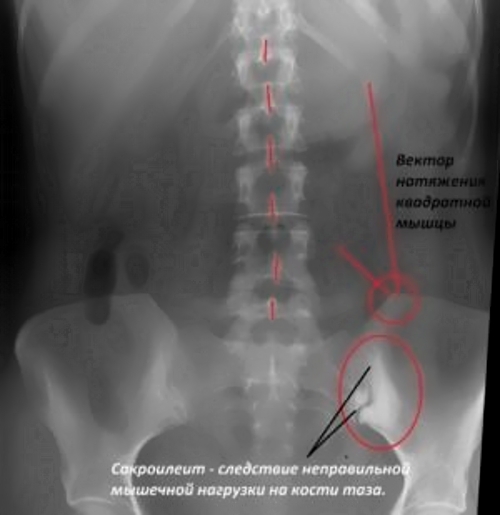

Первичный сакроилеит может развиться из-за травм. Даже незначительное повреждение может спровоцировать воспалительный процесс. Часто причиной сакроилеита становятся чрезмерные физические нагрузки на сустав. Перенос тяжестей, беременность и избыточный вес могут стать триггерами воспаления. Однако малоподвижный образ жизни также негативно сказывается на здоровье опорно-двигательной системы. Долгое сидение ослабляет кости таза и может привести к различным патологиям в области крестца. Кроме того, первичный сакроилеит может возникнуть из-за опухолей позвоночника или при инфицировании открытых травм. Некоторые патологии, возникающие в период внутриутробного развития, такие как врожденный вывих тазобедренного сустава, также могут способствовать развитию этого заболевания.

Неинфекционный (асептический) сакроилеит, вызванный нарушением функции сустава. Он развивается в результате травм или чрезмерных нагрузок на крестцово-подвздошное сочленение.